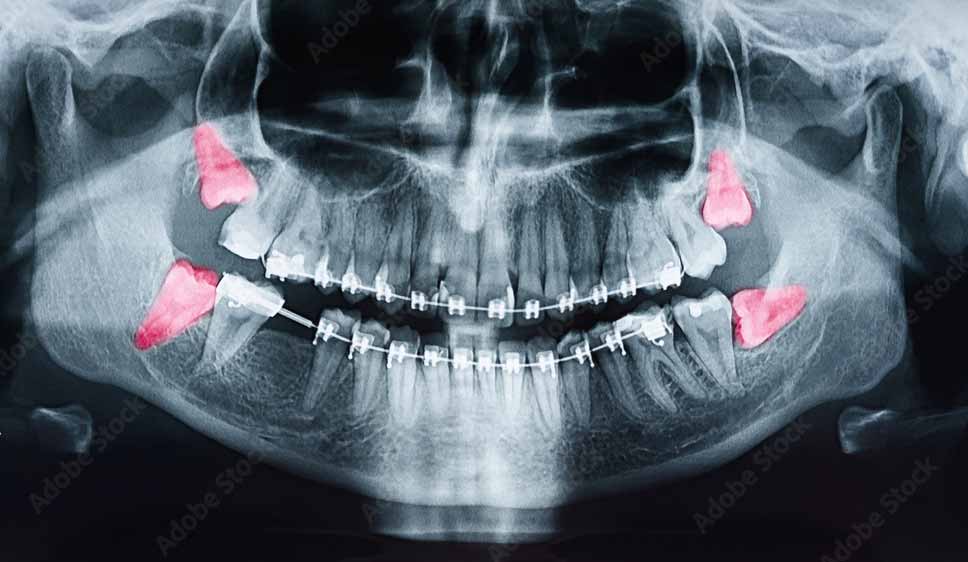

Wisdom teeth, also known as third molars, are the last four teeth to emerge in your jaw. They erupt in the upper and lower jaws at the most posterior areas, completing the set of 32 permanent teeth on both sides.

Generally, most people develop four wisdom teeth, but some or all of the third molars may never form, making them the most commonly missing teeth in adult mouths. In rare conditions, a person can have more than four wisdom teeth.

However, there are certain situations where the extraction of wisdom teeth is mandatory. According to the American Association of Oral and Maxillofacial Surgeons (AAOMS), “If there is insufficient anatomical space to accommodate normal eruption, the removal of such teeth at an early age is a valid and scientifically sound treatment rationale based on medical necessity.” They also state that “third molars that have links to causing disease should undergo removal.”

When a tooth fails to erupt and gets impacted, either partially or fully, and covered by gingiva or bone, it can cause a variety of issues that necessitate its removal, including: